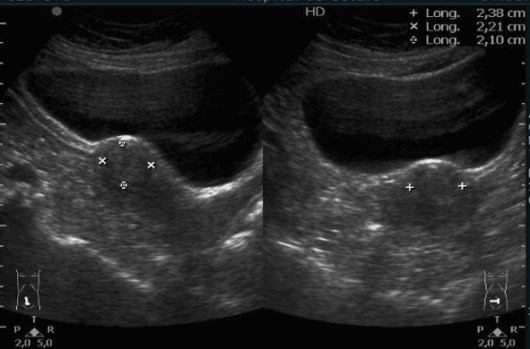

Aspecto ovárico niña neonatal.

En niñas recién nacidas podemos encontrar este aspecto en el ovario por hormonas maternas, se resuelven meses después.